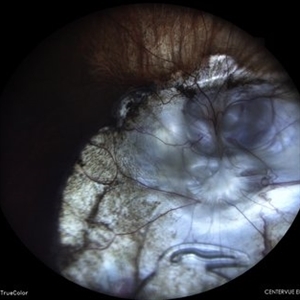

IOL in Vitreous Cavity Right Eye

Fundus infra-red image of a 47-year-old male with IOL in vitreous cavity right eye.

Photographer: Dr. Akansha Sharma-Retina Foundation, Ahmedabad

Condition/keywords: intraocular lens (IOL)